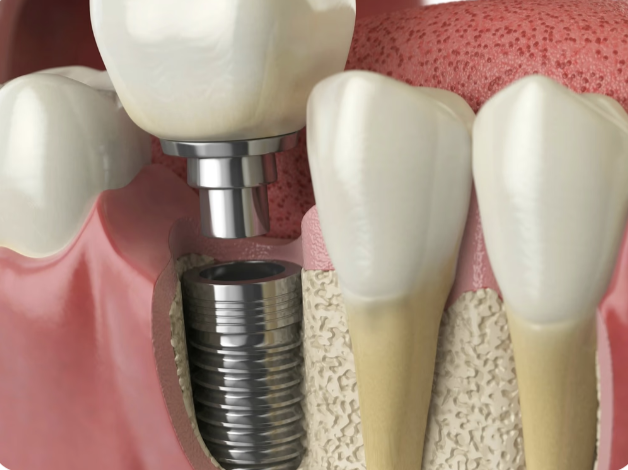

Dental Implants

At Pilbara Dental Studios, dental implants are common. They are permanent replacements that look and feel natural, fixed in your jawbone. Unlike bridges, nearby teeth don't get cut. An implant includes a titanium screw in the bone, holding a porcelain crown without using neighboring teeth.